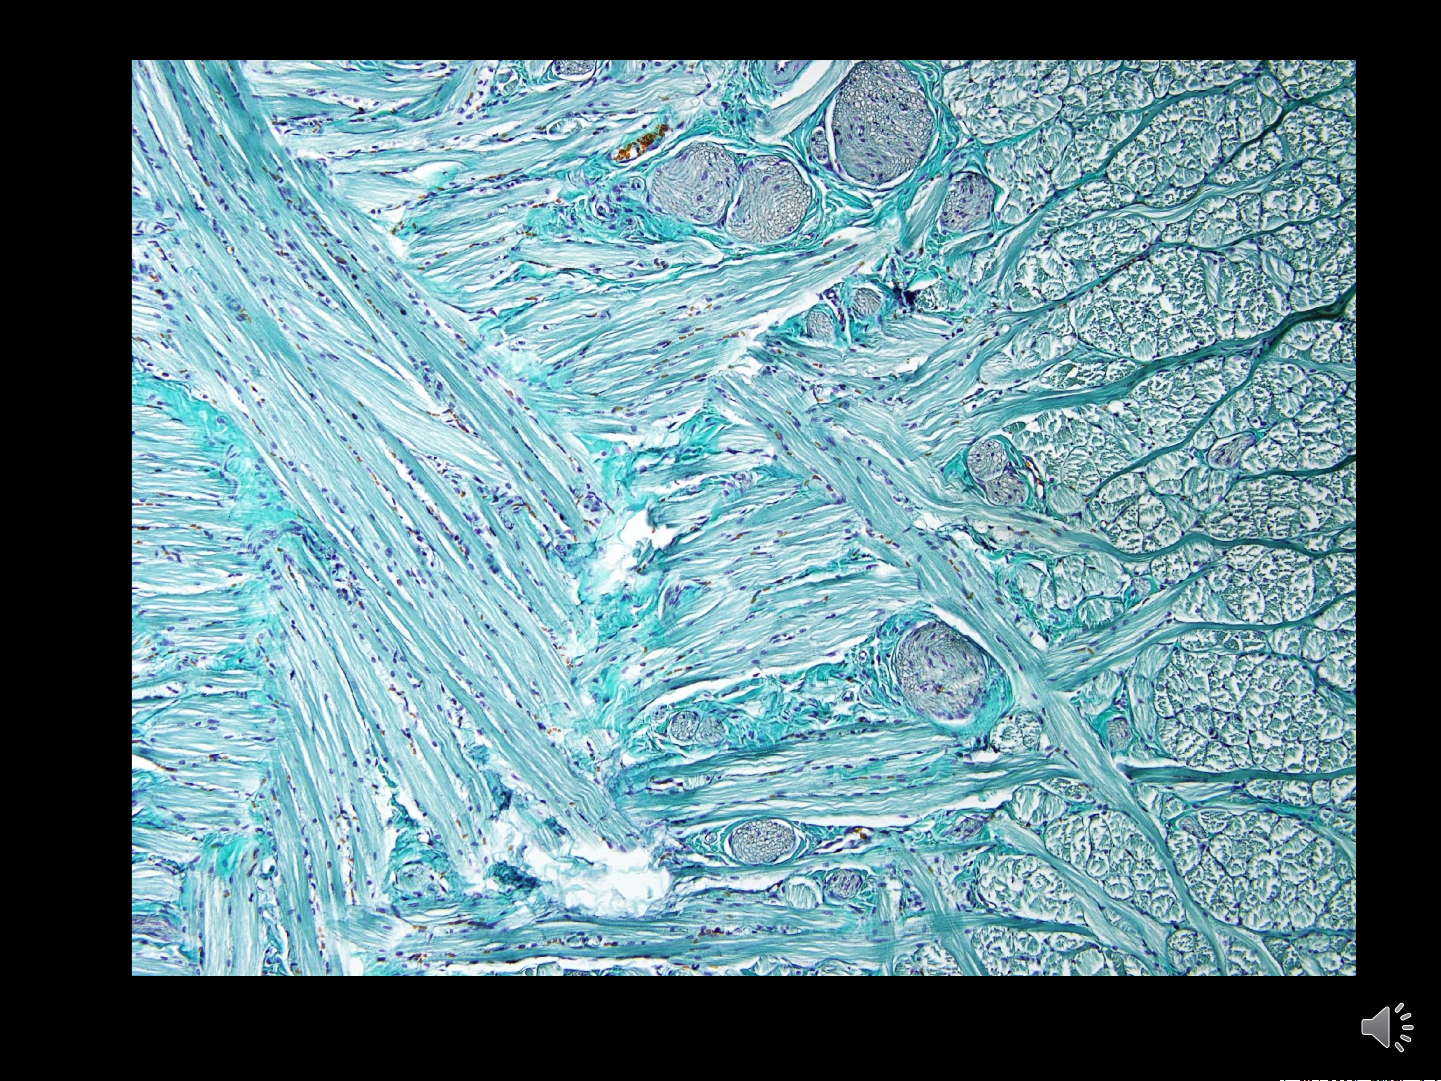

• Screen Shot 2022-09-24 at 22.38.37 Sự co cơ của cơ vân CƠ TIM • Có vân ngang

• Hoạt động co duỗi không

tuân theo sự điều khiển của ý muốn chỗ nối

• Tạo thành lưới🡪 chỗ nối:

đĩa nối, vạch bậc thang tế bào cơ tim • Khoang Henlé: khoang khoang helé

nằm giữa các nhánh kết

nối có chứa mô liên kết giàu mạch máu và mạch bạch huyết

• Tế bào cơ tim ( sợi cơ tim):

• Hình trụ, phân nhánh (100 - 150 μm, 10 - 20 μm)

• Nhân hình bầu dục ở giữa tế bào • Vạch bậc thang CƠ TIM CẮT DỌC Ti thể chiếm khoảng 40% thể tích bào tương (2% ở tế bào cơ vân) CƠ TIM CẮT NGANG CƠ TIM